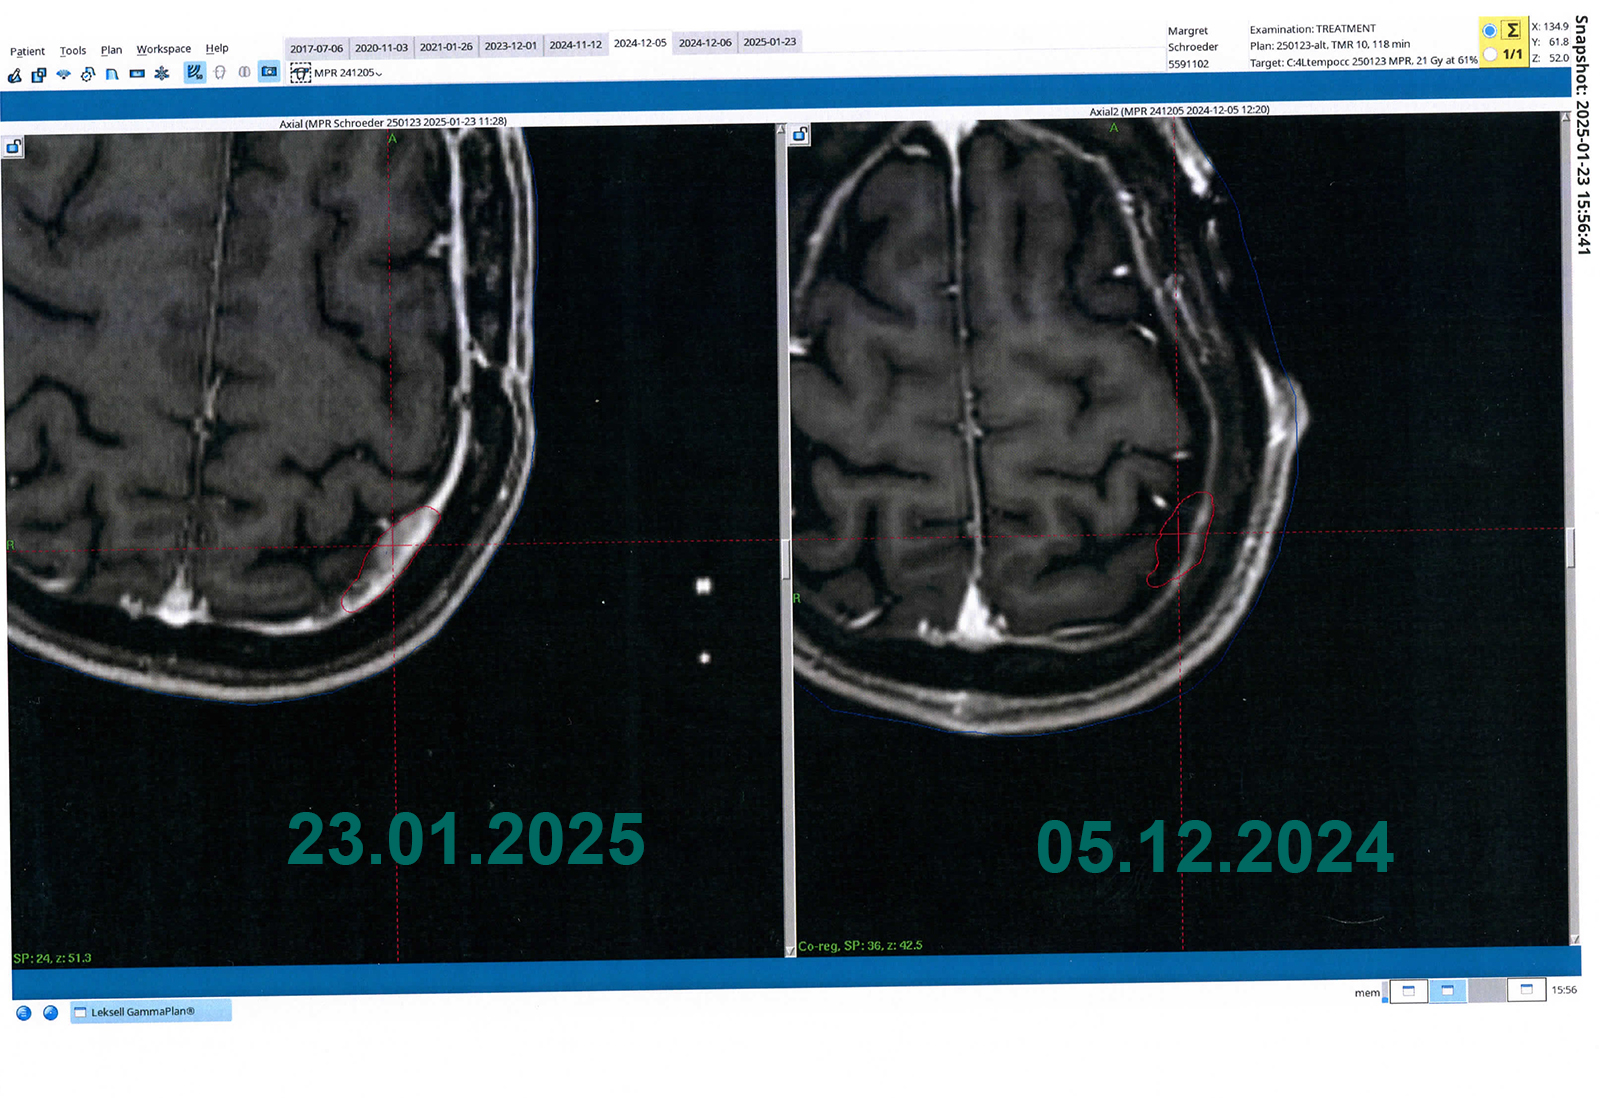

Schön zu sehen war, dass der bestrahlte Tumor kein Wachstum hatte - siehe Bilder vor dem Text.

• komplette Resektion des links frontobasalen Meningeoms, des links frontoorbitalen Meningeoms sowie des  im Jahr 2021 im Gamma Knife behandelten Meningeoms. Die weiteren oben beschriebenen Meningeoms sind unverändert.

26.01.2025: Gamma-Knife

Es werden  die folgenden Meningeome therapiert:

• #2 Konvexitätsmeningeom links temporalateral (8 x 5 x 7 mm)

• #3 Links tempora-medial ausgehend vom Tentorium unmittelbar oberhalb des Cavum Meckeli links (10 x 10 x 11 mm) Minimum

• #4 Links temporo- okzipital im okzipito parietalen Übergang (20 x 11 x 13 mm)

• #6 Links okzipito lateral (8 mm unterhalb von #4)